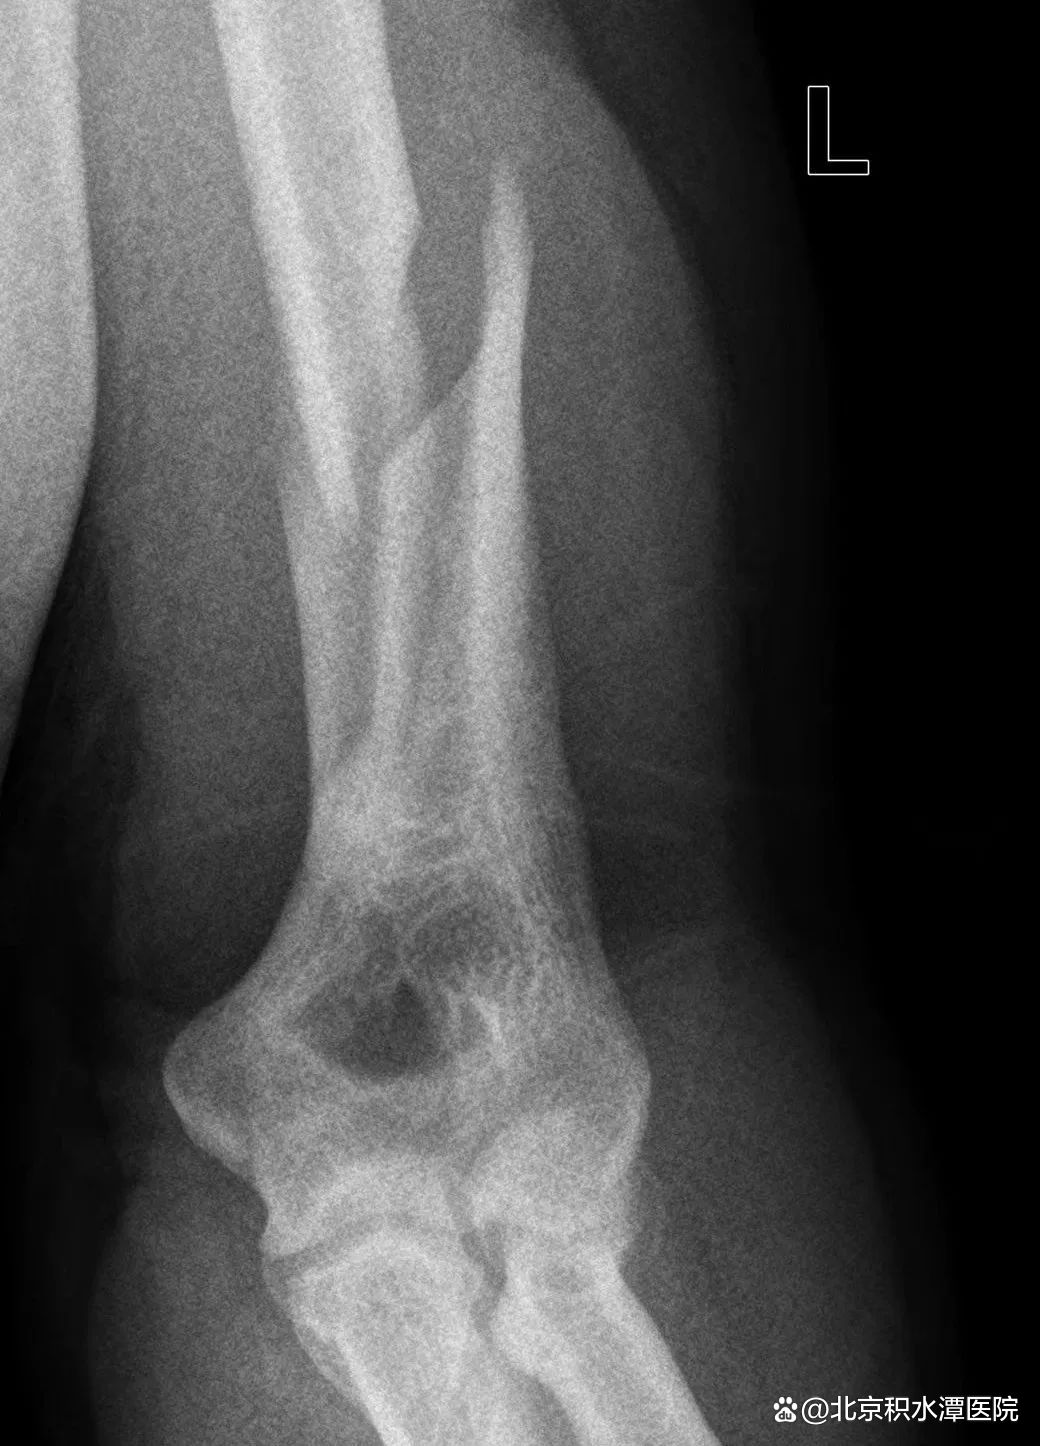

图|扳手腕导致的肱骨干骨折

由于存在共同的受伤机制,扳手腕导致的肱骨干骨折表现极为相似。这类骨折几乎都是肱骨远端三分之一螺旋形骨折,半数伴有蝶形骨折片,在AO/OTA分型中分别为12-A1型和12-B1型,可伴有桡神经损伤。